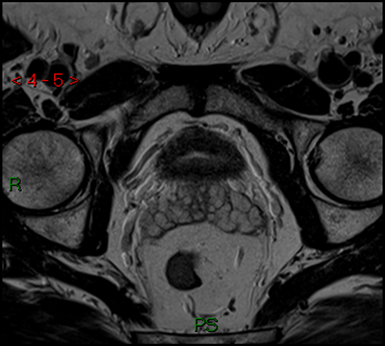

What is this MRI showing?

A pathology in the seminal vesicle